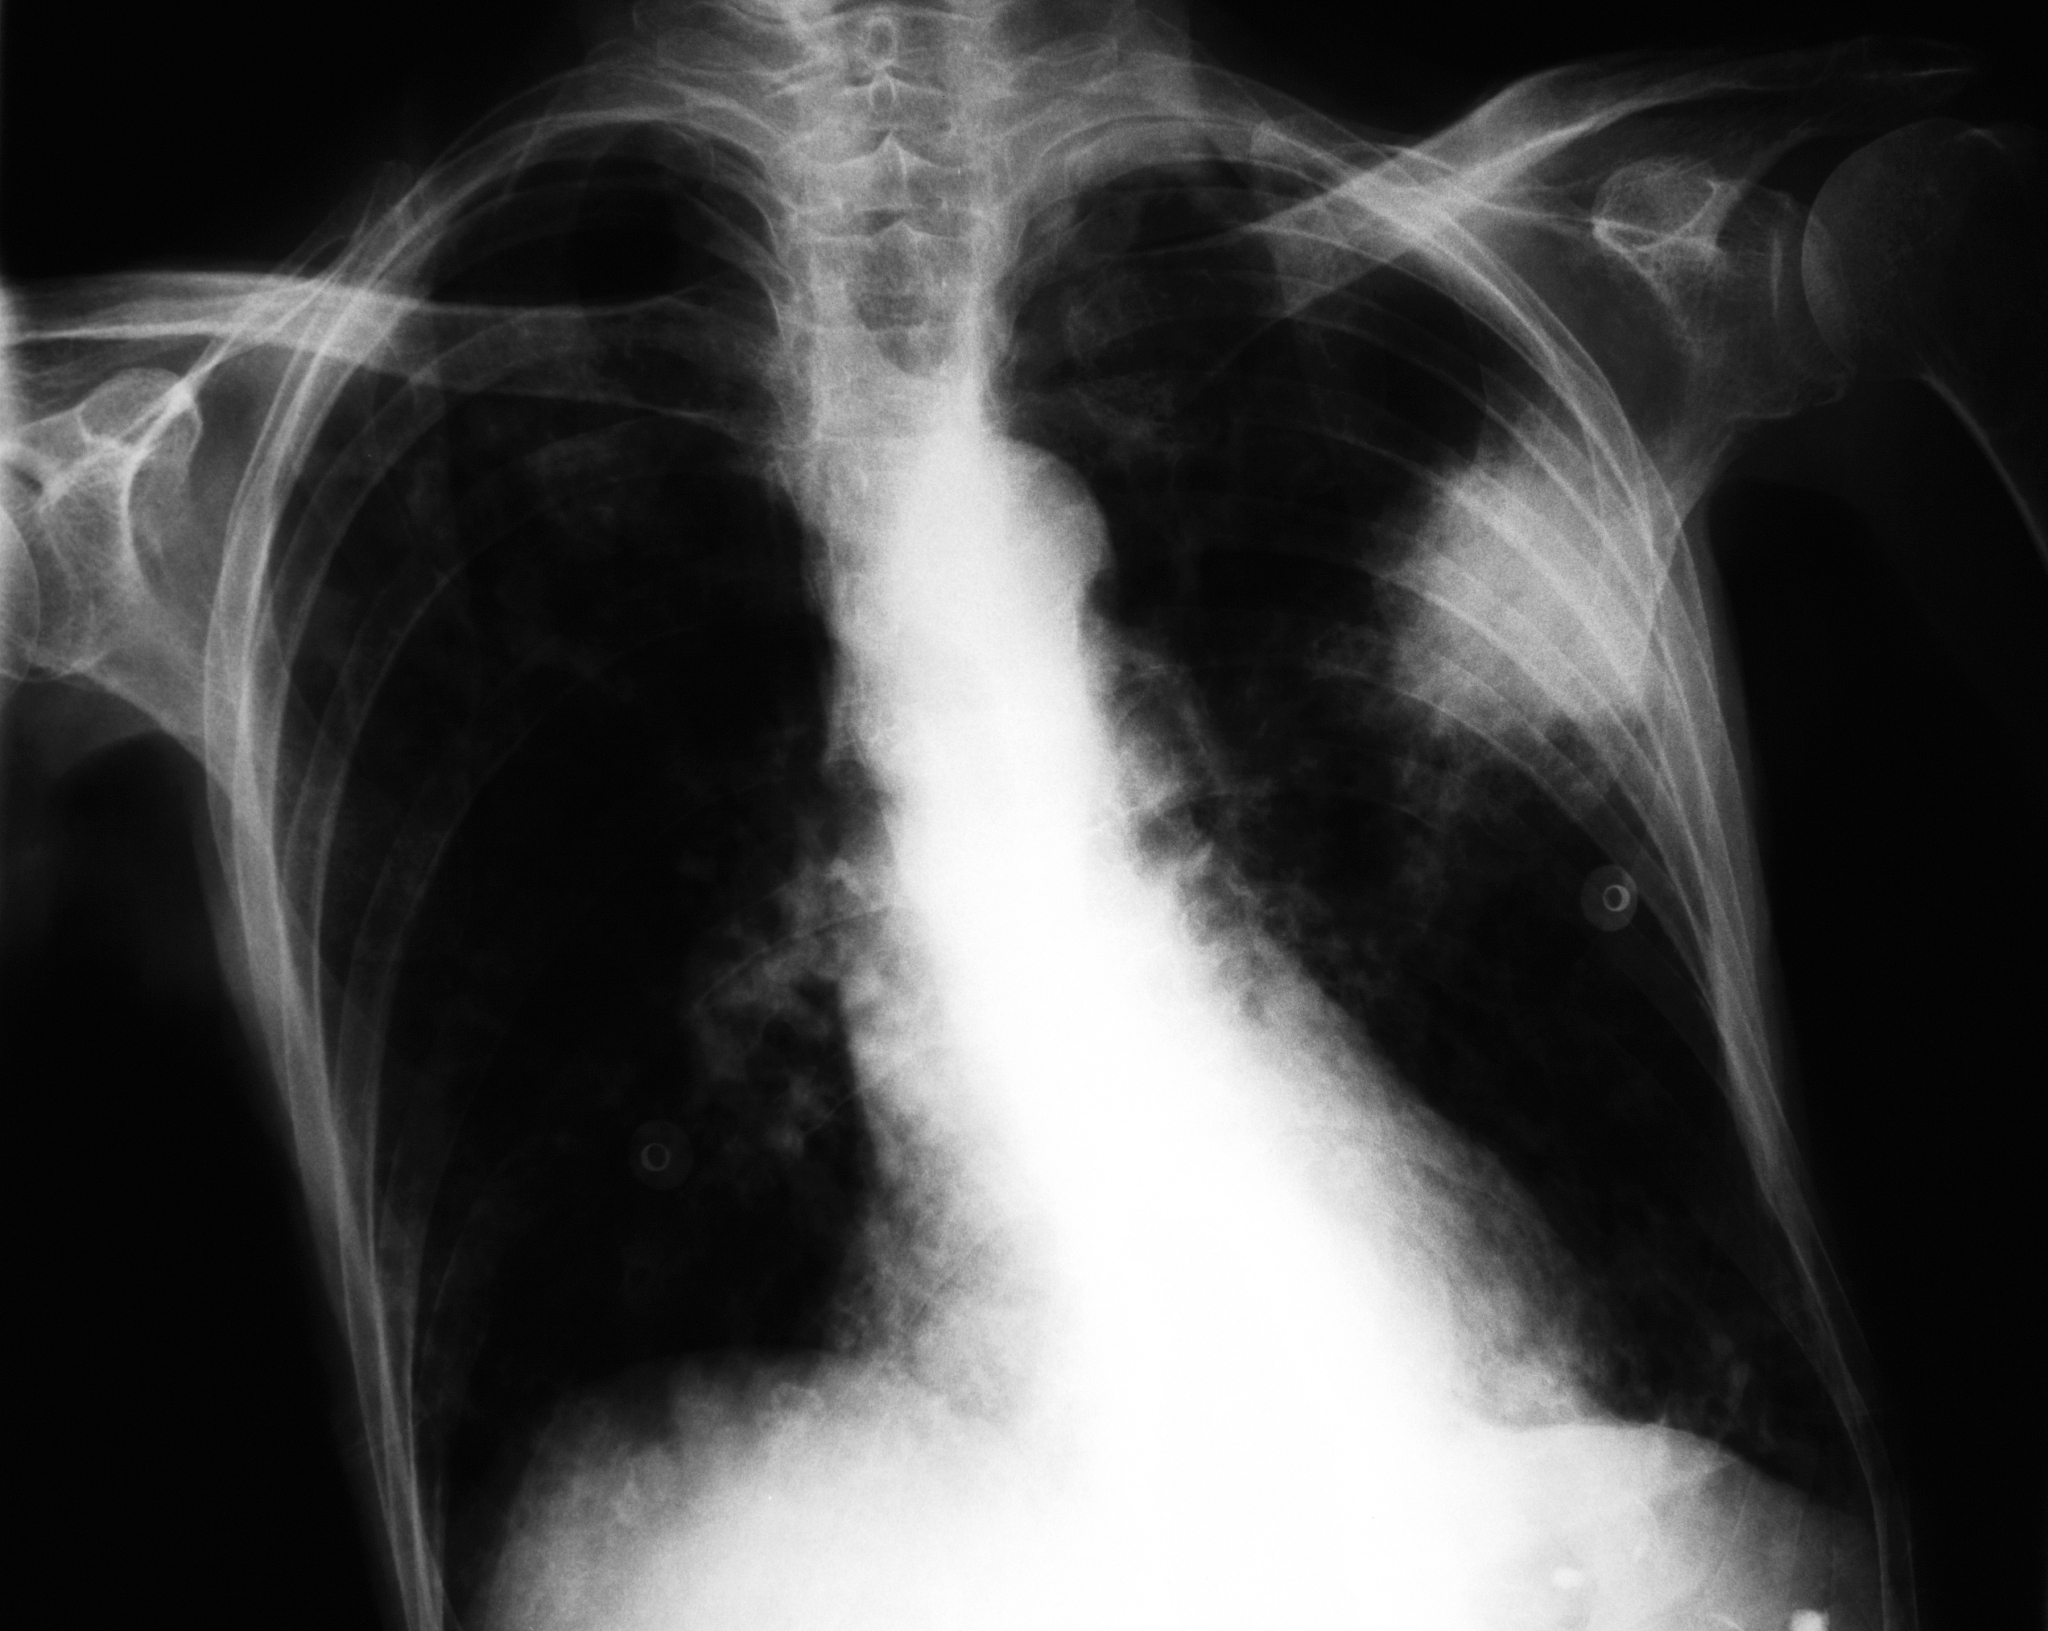

肺癌中晚期的影像学表现可以包括以下几个方面:

1. 肺实质病变:肺癌中晚期常常会出现大片的肺实质病变,表现为肺实质浸润、肿块或大片的结节状病变。

2. 淋巴结转移:肺癌中晚期常常会出现淋巴结转移,表现为肺门、纵隔、锁骨上、肺周围等区域的淋巴结增大、密度增高等改变。

4. 胸腔积液:肺癌中晚期常会导致胸腔积液的形成,表现为胸腔内积液的密度增高、积液量增多等。

5. 支气管阻塞:肺癌中晚期常常会引起支气管阻塞,表现为支气管扩张、肺段或肺叶不张。

总的来说,肺癌中晚期的影像学表现主要是肺实质病变、淋巴结转移、脏器转移、胸腔积液和支气管阻塞等。这些表现可以通过X线、CT、MRI等影像学检查来观察和评估。

肺癌中晚期影像学表现:X线、CT、MRI 检查揭示病变